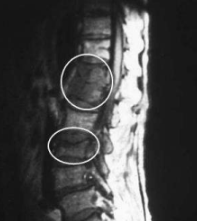

(八) 癌症轉移引起下背痛

一般轉移性之下背痛,屬於非機械性之下背痛,其症狀隨著轉移部位之嚴重性而加重,與身體軀幹之姿勢較無相關性。對一般口服止痛藥或物理治療之反應較不明顯 (Maccauro, 2011:107969;Leri, 2018:121-127)。(參見圖 8)

圖8 胸椎之癌症轉移變化(如圈區所示)